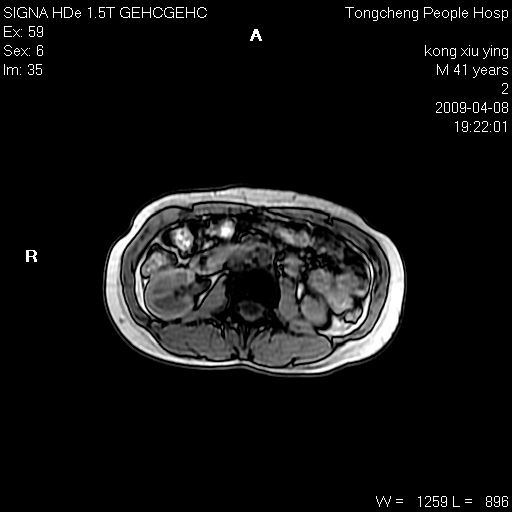

标题: CL1008:【经典】胆囊石榴籽样结石。 [打印本页]

标题: CL1008:【经典】胆囊石榴籽样结石。

女,41岁。健康体检——彩超提示:胆囊显示不清。平素健康,无不适感。

腹部mr扫描及mrcp,图像如下:

石榴籽样阴性结石,学习了!

胆囊石榴籽样结石。